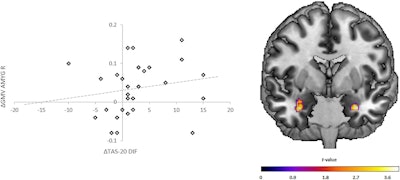

Gray-matter volume changes in the amygdala within patients and the association with improvements in alexithymia (Difficulty Identifying Feelings). (Left) Scatter plots depicting GMV changes (delta = t2-t1) within the cluster of the right amygdala (x = 32, y = −3, z = −27) on the y-axis correlated with changes (delta = t1-t2) in the Toronto Alexithymia Scale (TAS20) subscale Difficulty Identifying Feelings (DIF; rs = 0.321, p = 0.042) on the x-axis within the patient group. Line: regression slope. (Right) Coronal view (Montreal-Neurological-Institute coordinate y = 0) depicts the results of the paired t-tests (t1 vs. t2) in the patient group within the bilateral amygdala. Graphics, images, and caption courtesy of Translational Psychiatry via a Creative Commons License.

The group reported that more than half of the patients diagnosed with acute depression -- 19 of 30 -- had hardly any acute depressive symptoms after therapy, and that their brains had altered in a positive manner: Those with a greater increase in grey matter in the amygdala also showed a stronger reduction in their emotional dysregulation.